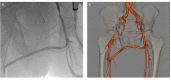

Presentation of case: The patient is an 83-year-old male who presents with severe sepsis, right lower quadrant and right leg pain. Additional past medical history is significant for rectal cancer status post resection and radiation therapy in 1997. Computed tomography (CT) on admission revealed a right iliopsoas muscle abscess, an inflamed Appendix and a pseudo aneurysm arising from the right external iliac artery. After consultations by multiple specialties, the plan was to proceed with percutaneous drainage of the abscess, antibiotic therapy and subsequent repair of the pseudoaneurysm. CT guided drainage of the iliopsoas abscess was performed with return of hemorrhagic fluid. Due to the concern of contained pseudoaneurysm rupture, the patient was taken for expedited repair. Due to the patient's frailty and hostile abdomen, we performed embolization of the right external iliac artery pseudoaneurysm with Amplatzer I plugs (St. Jude Medical, St. Paul MN) and left common femoral to right superficial femoral bypass with cryopreserved cadaveric femoral vein. Following pseudoaneurysm exclusion, continued percutaneous drainage and antibiotic therapy, the patient has done well with no further evidence of infection.